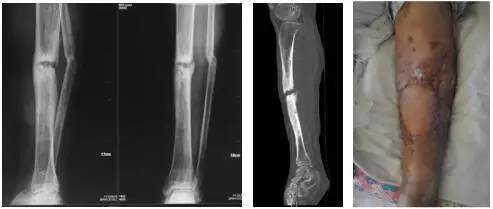

李某某,34岁男性。左胫骨骨折术后慢性骨髓炎13年。患者13年前因“胫腓骨骨折”于当地医院手术治疗,术后胫腓骨骨折处感染。随后多次手术清创并皮瓣覆盖创面、植骨、外固定架固定术等治疗,骨折仍未愈,皮肤遗留多个窦道。

术前,显示感染性骨不连,小腿遗留多个窦道